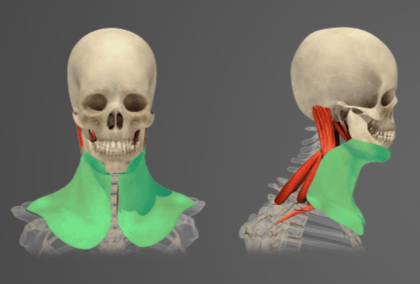

Question of

Určete:

-

sval čelní

-

sval tylní

-

šlachová přilba

-

svaly křídlové

-